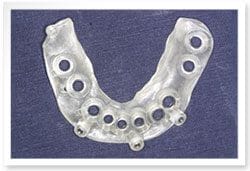

植牙過程

治療前

治療後